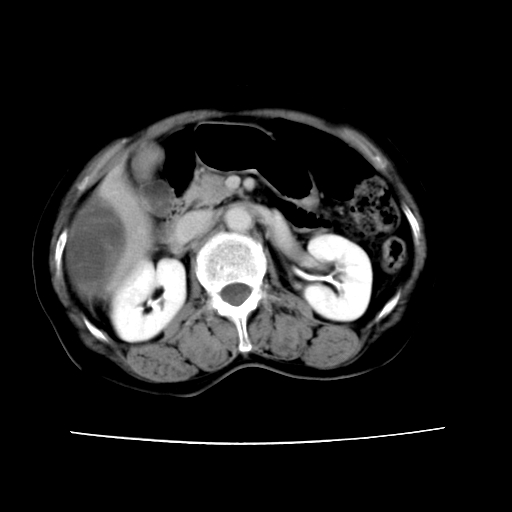

标题: CT16642:男62岁,突发性上腹部疼痛来诊。请讨论!

2008-6-10ct平扫

ct增强

6月份ct片显示肝内巨大混杂密度团块,伴包膜下积液(内含液液平面),增强多无明显强化。只能考虑肝占位病变,并肝内、血膜下血肿。肝ca并出血多见,而肝血管瘤并破裂出血少见。

6月份ct片显示肝内巨大混杂密度团块,伴包膜下积液(内含液液平面),增强多无明显强化。只能考虑肝占位病变,并肝内、包膜下血肿。肝ca并出血多见,而肝血管瘤并破裂出血少见。

从平扫+增强及治疗后复查片,病变明显缩小,不考虑肝癌出血可能,还是考虑为良性病变可能性大;单纯血肿并包膜下积液吧,病变强化没法解释,肝血管破裂出血吧,增强不符合典型血管瘤的表现,良性肿瘤破裂出血吧,复查片看来好像也不太支持(没做强化也不太好说)。本人还是考虑单纯肝内血肿并包膜下积液,强化是不是血管有外渗。